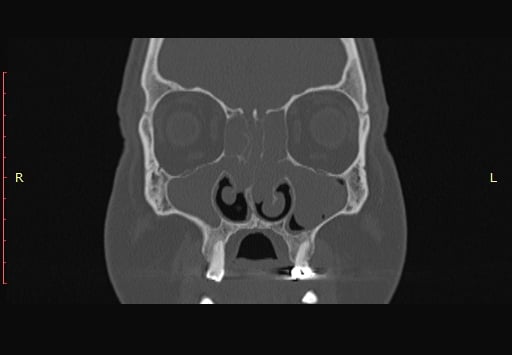

Problemi sa sinusima spadaju među najčešće kronične tegobe današnjice. Dugotrajna začepljenost nosa, glavobolje, smanjen osjet mirisa i ponavljajuće upale značajno narušavaju kvalitetu života. Dok većina pacijenata dobro reagira na konzervativnu terapiju (lijekove, ispiranja, sprejeve), kod određenog broja simptomi se uporno vraćaju. Tada se postavlja pitanje – je li vrijeme za operaciju?

Upravo tu dolazi endoskopska kirurgija sinusa (FESS – Functional Endoscopic Sinus Surgery), metoda koja je posljednjih desetljeća potpuno promijenila liječenje bolesti sinusa.

Kada je vrijeme za operaciju sinusa?

1. Kronični sinusitis (više od 12 tjedana simptoma)

2. Ponavljajuće akutne upale (više puta godišnje unatoč terapiji)

3. Nosni polipi koji uzrokuju smanjen njuh i začepljen nos

4. Komplikacije (upale oka, orbitalni apsces, širenje upale)

5. Loša kvaliteta života (nesanica, hrkanje, stalni umor, glavobolje)